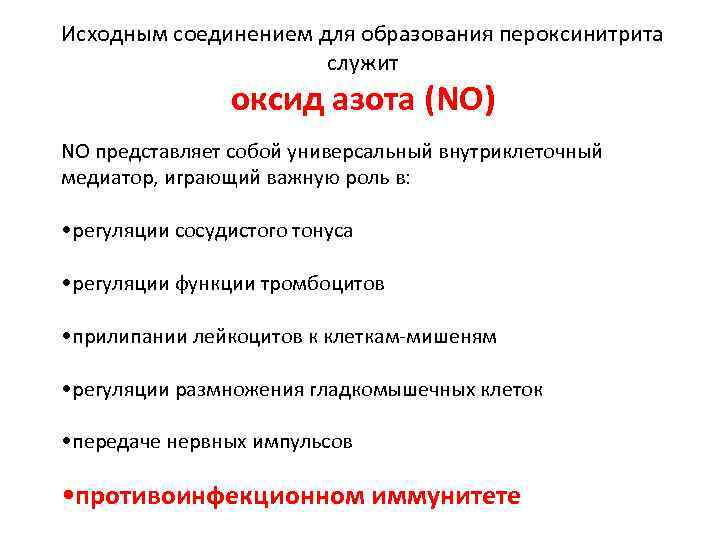

Исходным соединением для образования пероксинитрита служит оксид азота (NO) NO представляет собой универсальный внутриклеточный медиатор, играющий важную роль в: • регуляции сосудистого тонуса • регуляции функции тромбоцитов • прилипании лейкоцитов к клеткам-мишеням • регуляции размножения гладкомышечных клеток • передаче нервных импульсов • противоинфекционном иммунитете

Доноры NO усиливают разрушение: • цестод (Kanazawa T. et al. , 1993) • филярий (Rajan T. V. et al. , 1996; Thomas G. R. et al. , 1997) • шистосом (Oswald I. P. et al. , 1994; Ahmed S. et al. , 1997; Brunet L. R et al. , 1999) • токсокар (Fan C. -K. et al. , 2004)